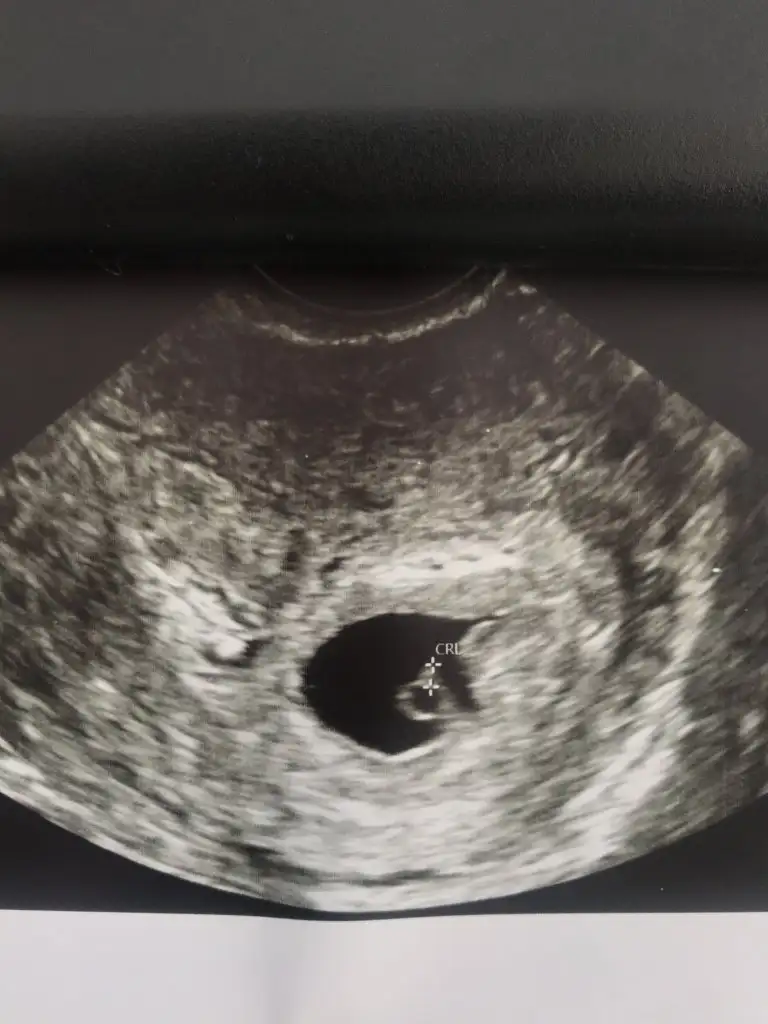

Dün tekrar kan testine girdim kendi isteğimle Vajinal ultrason da yaptırdım göremeyiz demelerine rağmen Çünkü kafamdaki Allah korusun ya dış gebelikse diye bir korku vardı hiçbir belirti yoktu ama beni anlayanlarınız vardır sürekli bir korku oluyor her aşamada çok şükür değerim inanılmaz yükselmiş biz 800 bekliyorduk 1500 küsürlere çıkmış ve minik de olsa tatlı bir kesecik gördük darısı sizin başınıza bütün sorularınızı buradan yanıtlayabilrim